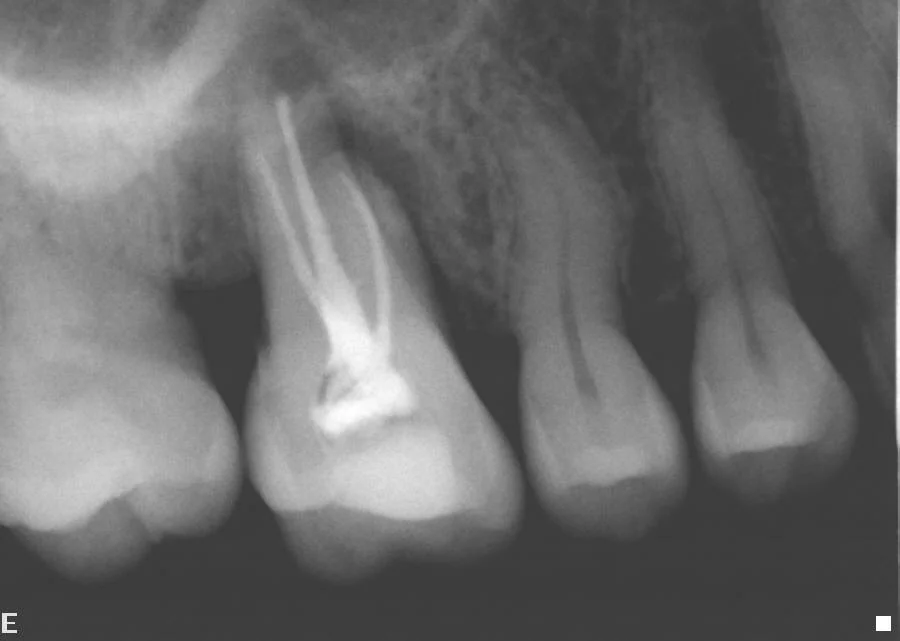

This shows an infected premolar with bone loss around the root; and a failed attempt at root treating a molar, with extensive bone loss. A decision was made to root treat the teeth and restore them.

The lower left premolar was root filled and turned out to have an unusual forked root structure ('bifid canal'). The infected molar root was re-root filled and a new crown made, saving both teeth.